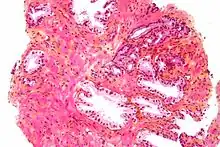

Micrograph showing inflamed prostate (H&E stain) with large amount of darker cells (leukocytes); area without inflammation seen on the left

Prostatitis is inflammation of the prostate gland. It can be caused by infection with bacteria, or other noninfective causes. Inflammation of the prostate can cause painful urination or ejaculation, groin pain, difficulty passing urine, or constitutional symptoms such as fever or tiredness.[28] When inflamed, the prostate becomes enlarged and is tender when touched during digital rectal examination. The bacteria responsible for the infection may be detected by a urine culture.[28]

Micrograph showing normal prostate cancer in the right upper aspect of image. HPS stain. Prostate biopsy.

Prostate cancer is one of the most common cancers affecting older men in the UK, US, Northern Europe and Australia, and a significant cause of death for elderly men worldwide.[33] Often, a person does not have symptoms; when they do occur, symptoms may include urinary frequency, urgency, hesitation and other symptoms associated with BPH. Uncommonly, such cancers may cause weight loss, retention of urine, or symptoms such as back pain due to metastatic lesions that have spread outside of the prostate.[28]

A digital rectal examination and the measurement of a prostate-specific antigen (PSA) level are usually the first investigations done to check for prostate cancer. PSA values are difficult to interpret, because a high value might be present in a person without cancer, and a low value can be present in someone with cancer.[28] The next form of testing is often the taking of a prostate biopsy to assess for tumour activity and invasiveness.[28] Because of the significant risk of overdiagnosis with widespread screening in the general population, prostate cancer screening is controversial.[34] If a tumour is confirmed, medical imaging such as an MRI or bone scan may be done to check for the presence of tumour metastases in other parts of the body.[28]